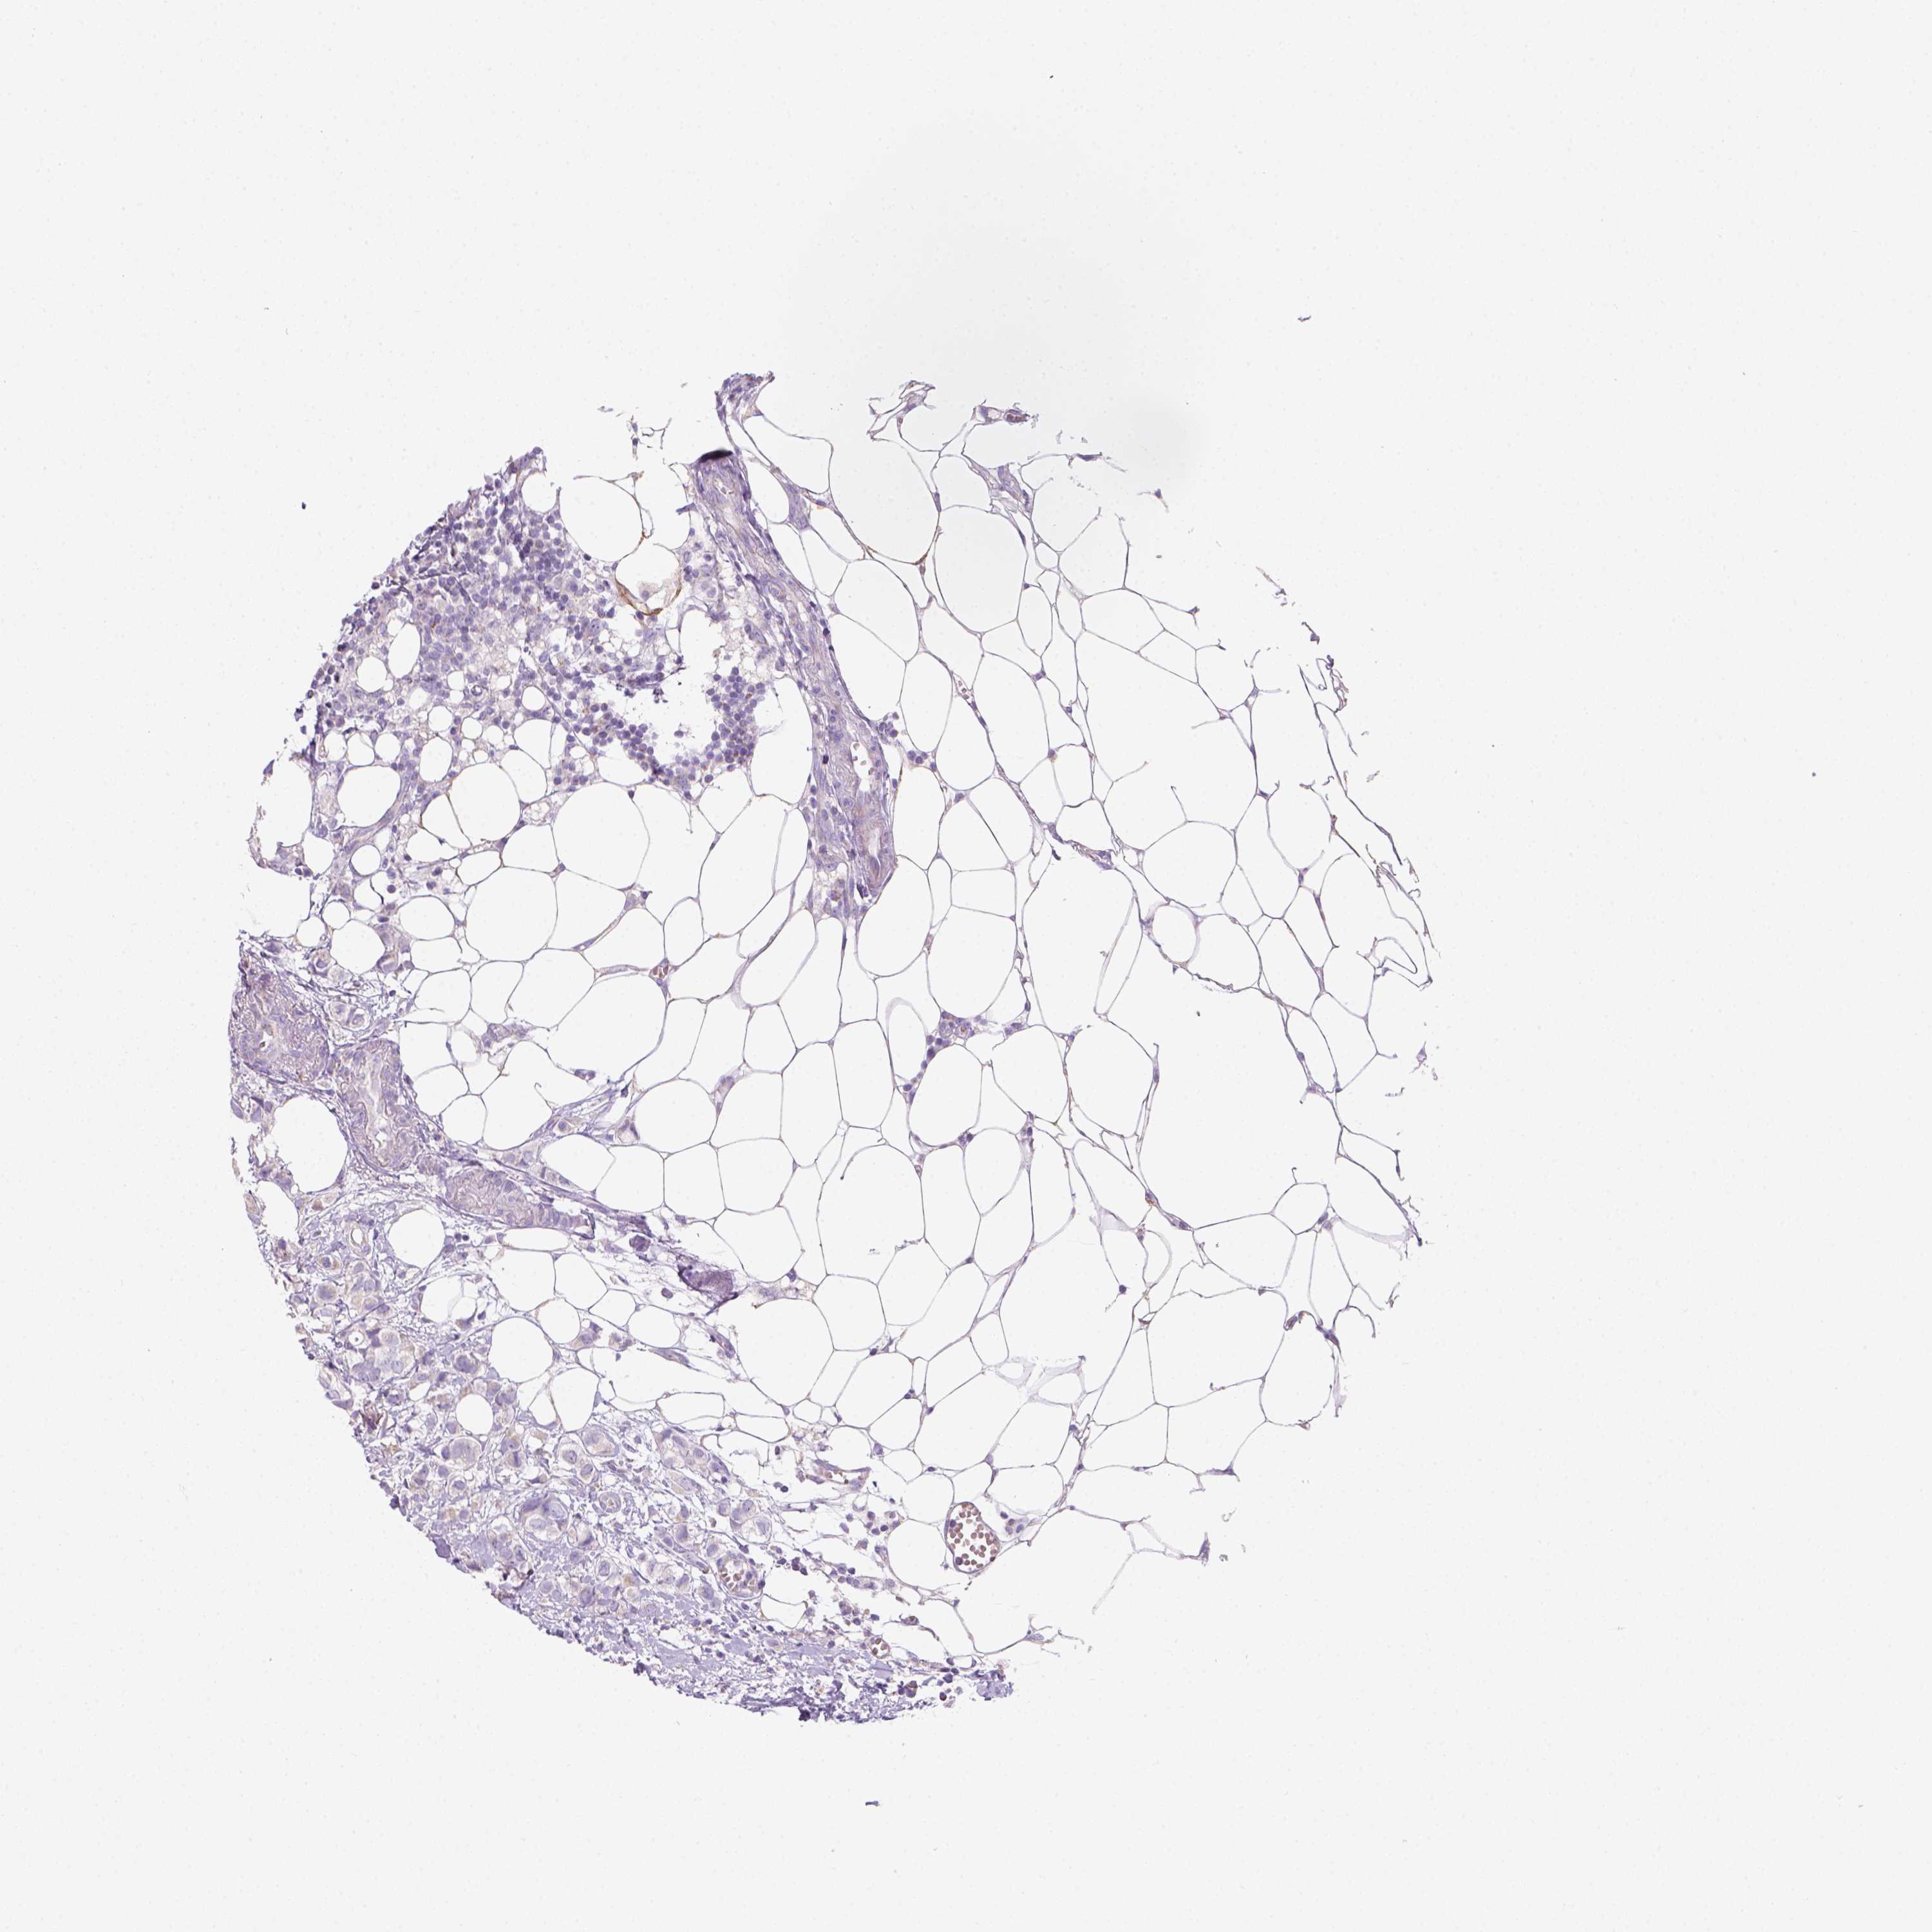

CANCER BREAST CANCER Show tissue menu

BRCA TCGA BRCA VALIDATION PROTEIN EXPRESSION

ANTIBODIES

AND

VALIDATION